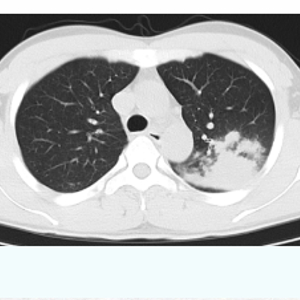

据介绍,患者是位32岁的年轻男子,发热咳嗽3天后来到宁波市中医院感染肺病科就诊。当时他的体温达到39℃,肺部CT显示左肺有大片炎症。

结合近期支原体肺炎多发的流行病学特点,医生考虑患者也是支原体肺炎。经相关检查,患者的血常规、降钙素原等指标提示感染严重,但他的血清支原体及衣原体抗体,以及痰培养检测,均未明确病原菌。最后做了支气管镜检查,提取肺部深部标本送检,通过病原宏基因检测,最终明确感染的是肺炎支原体。

经过中西医结合对症治疗10天后,肺部CT等检查提示,患者的肺炎较之前明显吸收,目前已好转出院。